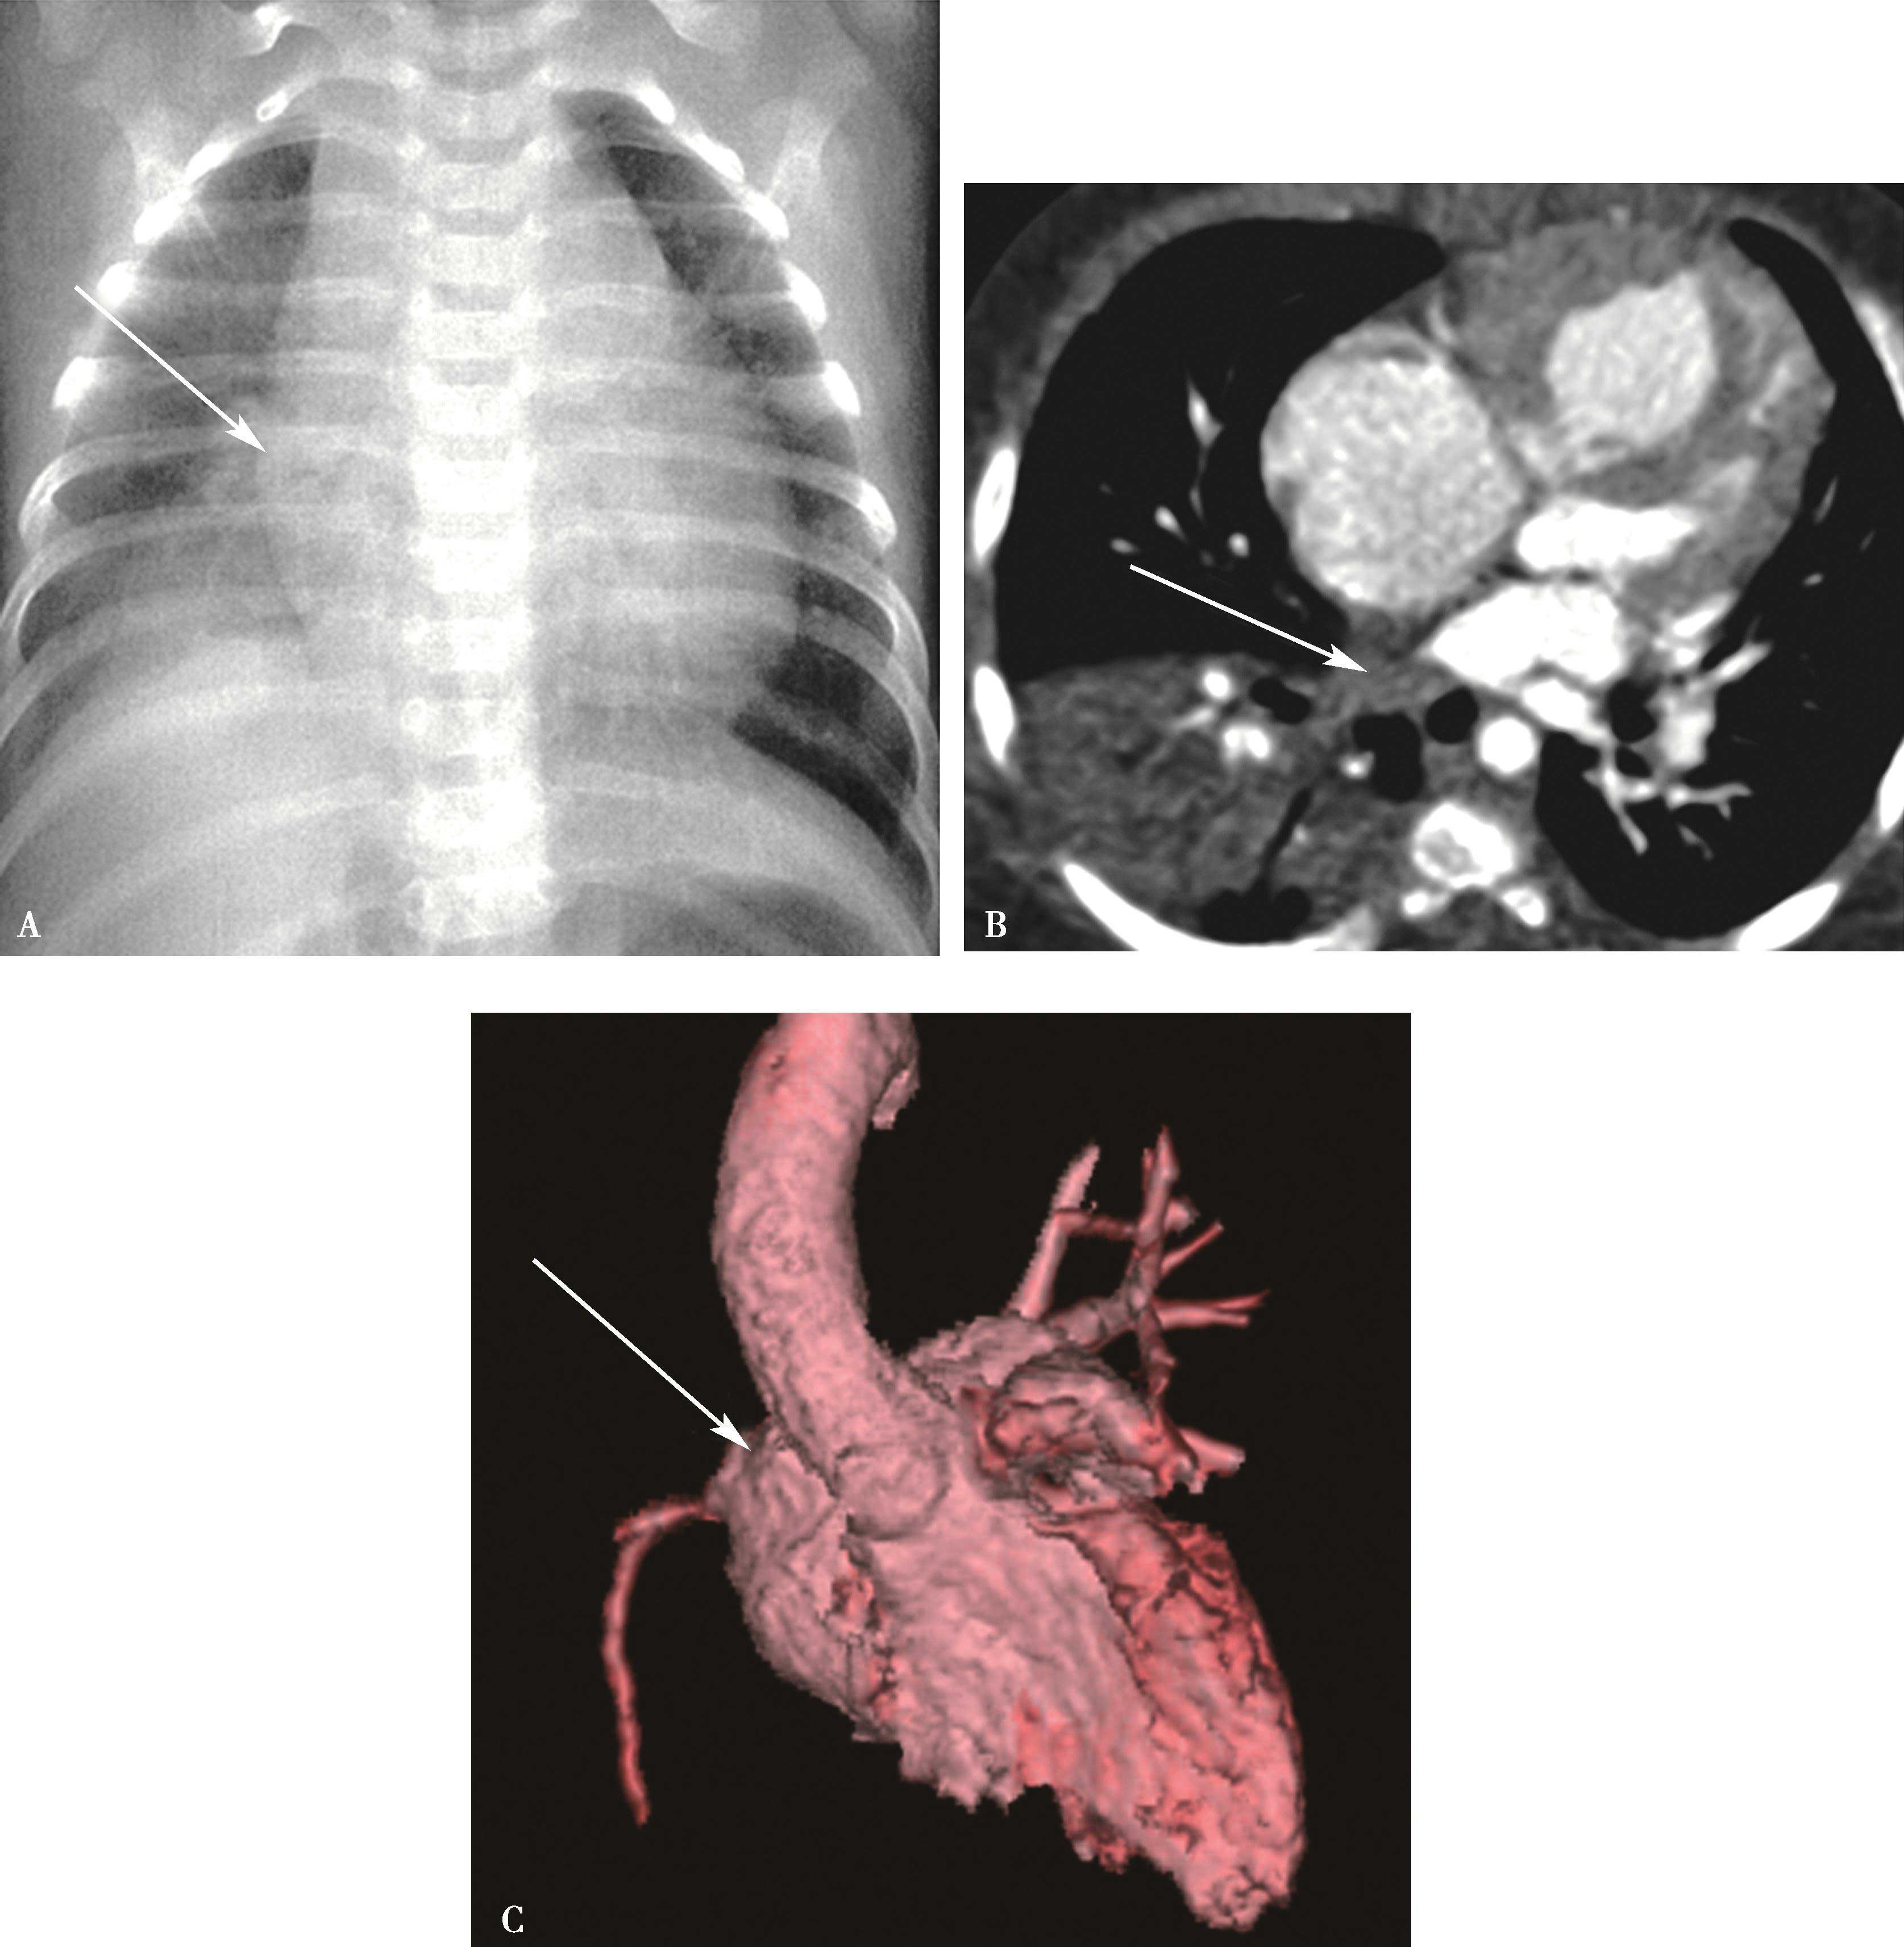

主要见于左-右分流先天性心脏病。此外,体动-静脉瘘、甲状腺功能亢进、发热、缺氧等右心排血量增加也可表现肺血增多。冠心病心肌梗死室间隔穿孔者可见肺血增多。少量左-右分流X线片多无阳性所见(图7-2-1)。

图7-2-1 女,29岁,心悸;超声心动图示:心内结构未见异常

X线片(A)示两肺血均匀增多,右心轻度增大;诊断为少-中等量左-右分流先天性心脏病,房水平可能性大。CTA(B)证实为部分性(心上型)肺静脉畸形引流。SVC:上腔静脉;LSPV:左上肺静脉;PA:主肺动脉;RA:右心房;RV:右心室

图7-2-4 女,37岁,大动脉炎(肺动脉型),右肺动脉重度狭窄。右侧肺血减少

A.心脏远达,右肺血减少,右心室增大;B.CTPA三维重建(VR),示右肺动脉重度狭窄(↑)

2.先天性一侧肺动脉缺如(图7-2-5)

图7-2-5 男,20岁,先天性一侧肺动脉缺如 右侧肺透过度增高,肺血明显减少(▲)。右膈升高(↑),右肺容积减小;右心增大,肺动脉高压

图7-2-8 女婴,3个月,气促,发绀;X线胸片示右下肺实变不张(A↑);右心增大。CTA:右下肺静脉闭锁(BC↑),右肺下叶实变不张,右心房室增大。肺动脉高压